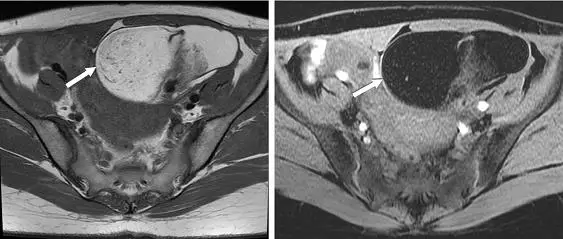

一位年輕女性接受磁振造影檢查發現卵巢腫瘤如圖,箭號所指之病灶,下列何者為最恰當之診斷? 圖片描述

影像包含兩張軸向MRI切片:

• 左圖(T1加權像):左側卵巢區域可見一巨大的囊性病灶,其內部部分組織呈高訊號(箭示處)。此種T1高訊號質常見於含脂肪或亞急性期血腫。

• 右圖(T1脂肪抑制像):同一位置的高訊號明顯被抑制,信號強度顯著下降。這說明該組織成分為脂肪,因脂肪抑制序列會專一性地抑制所有脂肪訊號。若為血腫(methemoglobin),T1脂肪抑制後仍維持高訊號,不會全部消失;若為巧克力囊腫(endometrioma)或黃體囊腫,主要成分為血液或血紅素衍生物,也不會在脂肪抑制序列中完全降訊。

MRI箭示處在T1加權像上的高訊號於脂肪抑制序列被完全抑制,證實病灶含大量脂肪,此為成熟囊性畸胎瘤(dermoid cyst)的特徵表現。其他血性病灶或巧克力囊腫雖也可在T1呈高訊號,但無法於脂肪抑制序列顯著失號,故均可排除。